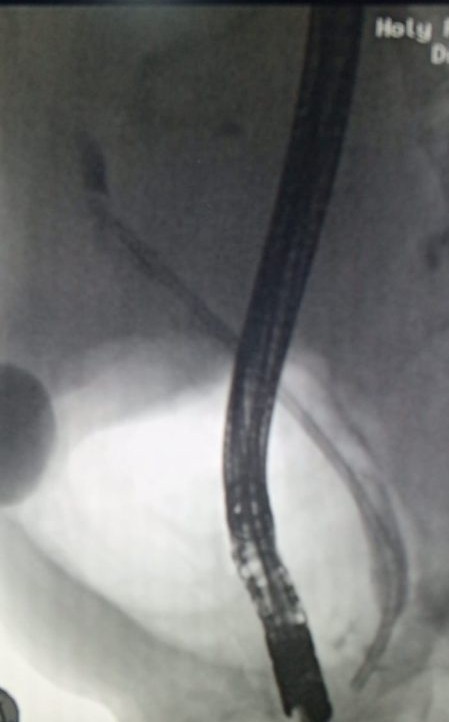

ERCP - Department of Gastroenterology, HFH

H/O Jaundice Pain RHC